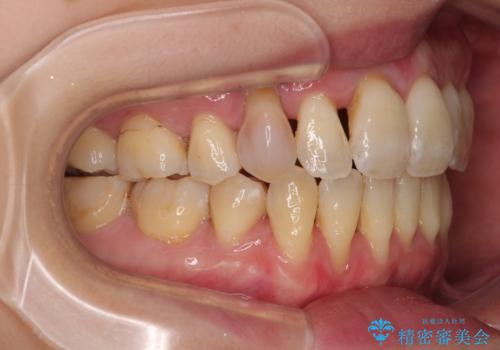

歯根露出が顕著であったため、歯の移動は早く、スムーズに治療を終えられるかと思いましたが、歯槽骨が硬く、治療は長期間に及びました。

過剰に力をかけ続ける事態となり、一部の歯では変色したり、神経が失活したりとトラブルが続きました。

それでも当初とは比べものにならないほど、綺麗な歯列に仕上げることができました。